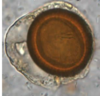

Taenia solium Cysticercus cellulosae (larval stage)

Cysticercosis Infective vs diagnosic?

Infective stage: embryonated eggs Diagnostic stage: cysticercus (imaging,